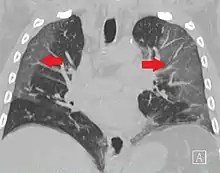

Ground-glass opacity (GGO) is a finding seen on chest x-ray (radiograph) or computed tomography (CT) imaging of the lungs. It is typically defined as an area of hazy opacification (x-ray) or increased attenuation (CT) due to air displacement by fluid, airway collapse, fibrosis, or a neoplastic process.[1] When a substance other than air fills an area of the lung it increases that area's density. On both x-ray and CT, this appears more grey or hazy as opposed to the normally dark-appearing lungs. Although it can sometimes be seen in normal lungs, common pathologic causes include infections, interstitial lung disease, and pulmonary edema.[2][3]

Ground-glass opacity is most often used to describe findings in high-resolution CT imaging of the thorax, although it is also used when describing chest radiographs. In CT, the term refers to one or multiple areas of increased attenuation (density) without concealment of the pulmonary vasculature. This appears more grey, as opposed to the normally dark-appearing (air-filled) lung on CT imaging. In chest radiographs, the term refers to one or multiple areas in which the normally darker-appearing (air-filled) lung appears more opaque, hazy, or cloudy. Ground-glass opacity is in contrast to consolidation, in which the pulmonary vascular markings are obscured.[3][5] GGO can be used to describe both focal and diffuse areas of increased density.[5] Subtypes of GGOs include diffuse, nodular, centrilobular, mosaic, crazy paving, halo sign, and reversed halo sign.[6]

CT image showing diffuse GGOs throughout both lungs. An abscess is also noted in the right lung (screen left). - Adenocarcinoma in situ of the lung